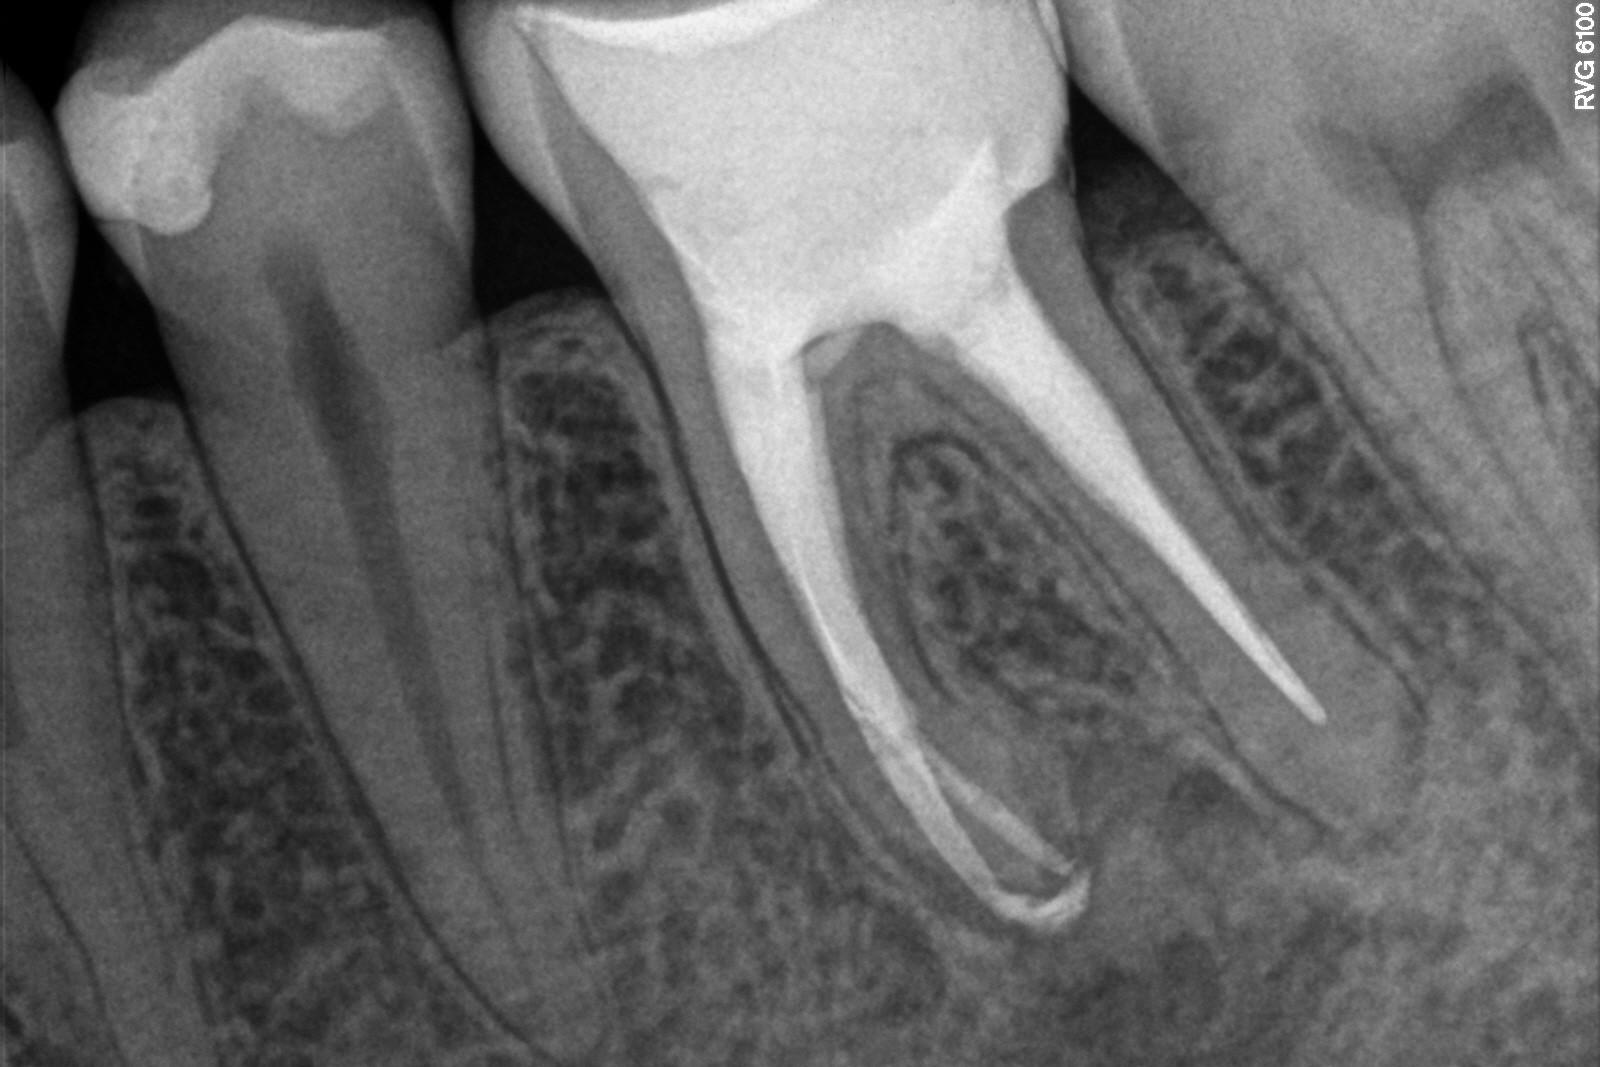

W przypadku zaawansowanych postaci zapaleń miazgi oraz zapalenia tkanek okołowierzchołkowych obraz radiologiczny jest warunkiem rozpoznania. W takiej sytuacji standardem diagnostycznym są zdjęcia przylegające zęba, często wykonywane przy użyciu radiowizjografii na fotelu stomatologicznym w trakcie leczenia zęba. Przydatne jest również badanie RTG OPG pantomograficzne, które pokazuje w dwuwymiarowym obrazie zarówno uzębienie, jak i cały układ kostny szczęki oraz żuchwy.

Stożkowa tomografia komputerowa CBCT, ze względu na dokładne, trójwymiarowe obrazowanie 3D, bez zniekształceń ukazuje szczegóły anatomii zęba oraz okolicznych tkanek, wyjaśniając nierzadko problemy niemożliwe do zdiagnozowania standardowymi metodami.

Na podstawie zdjęcia rentgenowskiego określa się kształt i długość kanału bądź za pomocą specjalnego urządzenia mierzy się jego długość. Potem lekarz otwiera wejścia do kanału, chroniąc ząb koferdamem, czyli specjalną gumą, zapewniającą sterylność oraz chroniącą przed środkami chemicznymi służącymi do oczyszczania kanału. Używa się do tego zarówno specjalistycznego sprzętu, jak i nowoczesnych mikroskopów, pozwalających na uzyskanie dokładnego obrazu leczonego zęba. Ostatnią czynnością jest wypełnienie materiałem światłoutwardzalnym i zabezpieczenie zęba przed dostaniem się i rozwojem bakterii mogących wywołać wtórny stan zapalny.

By uniknąć niedokładności leczenia, oprócz sumiennego wykonania procedur należy diagnostycznie kontrolować każdy etap leczniczy przy użyciu rtg. Szansą dla niedokładnie wypełnionego kanałowo zęba jest jego powtórne leczenie endodontyczne, zwane REENDO.